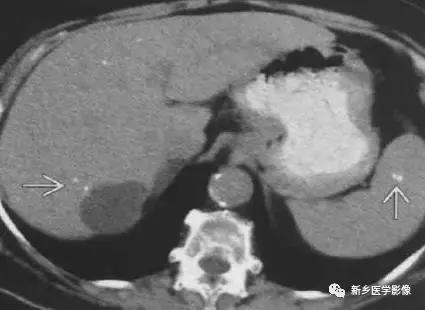

脾和肝肉芽肿

主要表现为点状的钙化,CT显示清晰,腹部平片有时候表现不明显